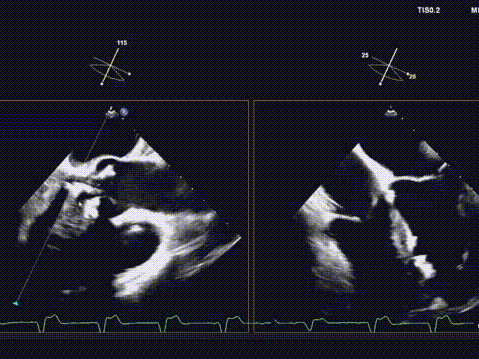

快速起搏下初次释放瓣膜,瓣膜开口形态不好,位置偏高;

遂回收瓣膜,重新跨瓣并调整瓣膜释放位置后;

快速起搏下再次释放瓣膜至工作位,超声评估开口形态可,位置深度满意;

遂150快速起搏下完全释放瓣膜;

观察无瓣膜移动,回撤导丝后撤出系统;

术后超声评估,瓣膜位置深度满意,形态可,微量瓣周漏,最大血流速度1.53m/s,平均跨瓣压差4mmHg。